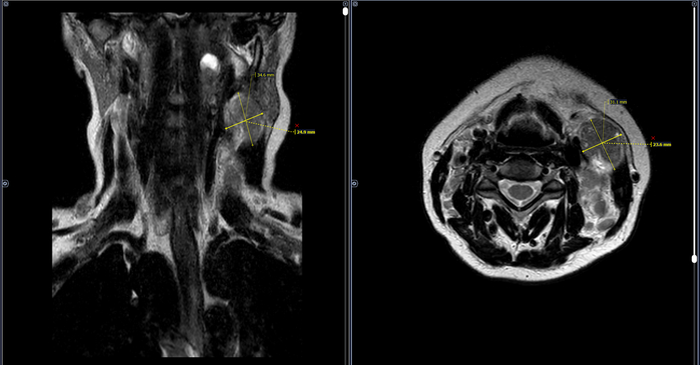

Изображения и частично текст взяли с радиопедии radiopaedia.org. 1 МРТ Т1, 2 МРТ Т2 (кейс 1), 3 - КТ с контрастом (кейс 2)

Магнитно-резонансная томография (МРТ)

Ключевые МР-признаки:

T1-ВИ: Обычно гиперинтенсивный сигнал (за счет меланина и/или крови).

T2-ВИ: Часто гипоинтенсивный.

T1-ВИ с контрастом: Контрастирование по периферическому (ободковому) или гетерогенному диффузному типу.

*T2 (GRE) / SWI:** Важный диагностический признак. Выраженные артефакты магнитной восприимчивости (гипоинтенсивный "ободок") связаны в первую очередь с геморрагическим компонентом (гемосидерин), а не с меланином, который обладает слабым диамагнитным эффектом.

Артефакты восприимчивости встречаются в 42% случаев метастазов меланомы (для сравнения, при метастазах рака легкого — лишь в 8%).

Некоторые мелкие метастазы могут быть видны только на T2*/SWI, однако интерпретировать изолированные гипоинтенсивные очаги на этих последовательностях следует с осторожностью.